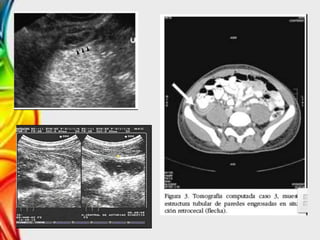

• Ecografía

– Sensibilidad y especificidad >90%

– Imagen en Diana o en ojo de buey.

– Criterios ecográficos para el diagnostico:

• Grosor de la pared >6mm

• Distensión luminal

• Masa compleja en FID

– Debe visualizarse un apéndice normal para descartar apendicitis.

• TAC

– Sensibilidad y especificidad >95%

– Mejor visualización de los apendicolitos

– Útil para guiar un drenaje percutáneo

• Ecografía (sensibilidad de 88%)

– Masa tubular en proyecciones longitudinales

– Aspecto en diana en proyecciones transversales

• Radiografía Simple –5-10% se observa fecalitos. – Niveles hidroaéreos • Ecografía – Sensibilidad y especificidad >90% – Imagen en Diana o en ojo de buey. – Criterios ecográficos para el diagnostico: • Grosor de la pared >6mm • Distensión luminal • Masa compleja en FID – Debe visualizarse un apéndice normal para descartar apendicitis. • TAC – Sensibilidad y especificidad >95% – Mejor visualización de los apendicolitos – Útil para guiar un drenaje percutáneo Estudios de imagen

Diagnóstico • Anamnesis yexploración física. • Ecografía (sensibilidad de 88%) – Masa tubular en proyecciones longitudinales – Aspecto en diana en proyecciones transversales • Enemas de contraste (signo de Muelle)